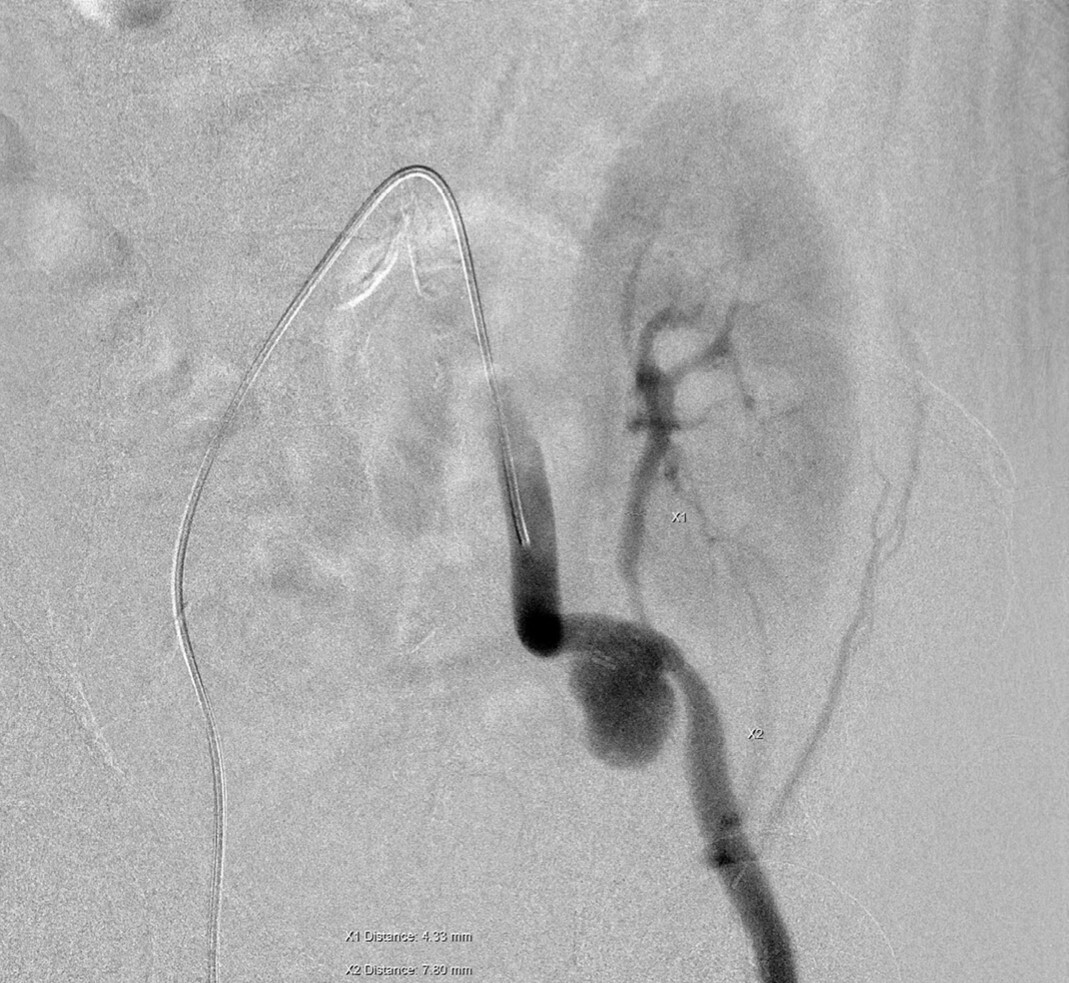

A 56-year-old male with end-stage renal disease who began hemodialysis in 2020 and underwent a cadaveric kidney transplant (right kidney to left iliac fossa) on 5 December 2023 developed a pseudoaneurysm at the anastomotic site on the left external iliac artery (EIA). This was complicated by recurrent urinary tract infection, blood stream infection, and declining renal function, with serum creatinine increasing to 4.8 mg/dL in April 2024. A duplex ultrasound identified a mass lesion, confirmed by angiography (Figure 1) as a pseudoaneurysm at the EIA anastomosis. A hybrid strategy was implemented, combining a femoral–femoral bypass using an 8 mm Geotex polytetrafluoroethylene (PTFE) graft. This was followed by percutaneous transluminal angioplasty with stenting of the graft renal artery and the EIA using covered 6.0 × 50 mm and 8.0 × 50 mm Viabahn stents to exclude inflow to the pseudoaneurysm. Finally, coil embolization of the left pseudoaneurysm and left common iliac artery was performed.